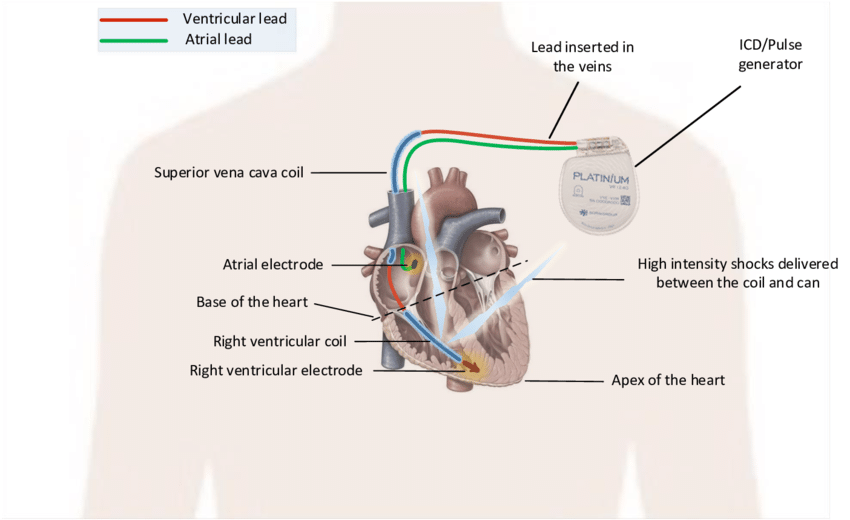

Overview

Package includes:

Days in hospital : 3 Days (For patient and one attendant)

Days in hotel : 10 Days (For patient and one attendant)

Room type in hospital : Shared

Room type in hotel : Private

Hotel category: Standard

Value added benefits of the ICD:

Ø Doctor consultation charges

Ø Lab tests and diagnostic charges

Ø Room charges inside hospital during the procedure

Ø Surgeon Fee

Ø Nursing charges

Ø Hospital surgery suite charges

Ø Anesthesia charges

Ø Routine medicines and routine consumables (bandages, dressings etc.)

Ø Food and Beverages inside hospital stay for patient and one attendant.

Extra benefits:

ü Interpreter

ü Visa assistance

Ø Site tourism of the city

Ø Follow up with the doctor

Ø Airport pick up and drop

Ø Free online consultation with the doctor

Ø Priority appointments with the doctor

Ø Room upgrade from sharing to private